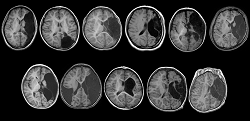

3-3. 結果: 手術、術後の発作転帰、機能転帰

図4

• 7例で半球離断術、3例で半球後方の離断術、1例で後頭葉の離断術を施行した。

• 11例中10例で術後の良好な発作転帰(発作の消失あるいは稀発)(Engelのclass I ないしはII)が得られた。

• 術後に新たな神経脱落症状を呈した症例はなかった。